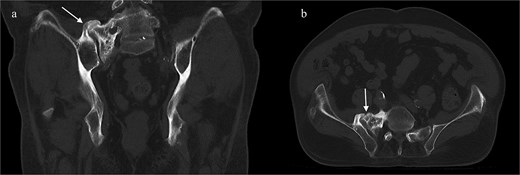

He was discharged home on postoperative day two, with instructions to remain toe-touch weight-bearing for three weeks. He was seen in the office two weeks after surgery. Lateral and antero-posterior pelvic radiographs showed good position of all hardware (Fig. 4). He reported mild incisional pain, but his preoperative pain had significantly improved. He was able to ambulate for the first time in years. Pain relief remains sustained three months after surgery.

Postoperative lateral (left) and AP (right) re-demonstrated good placement of the hardware.